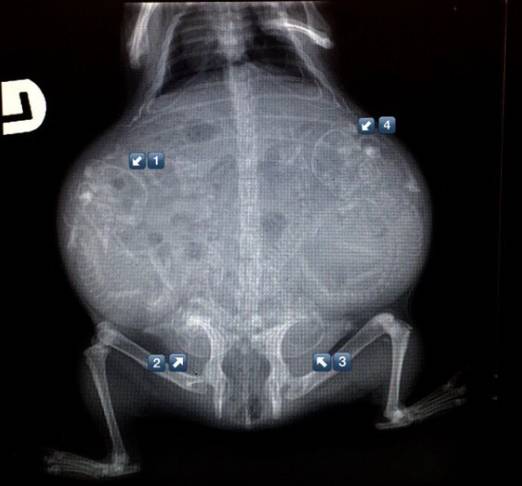

1. 狗狗。

能数得出是几胞胎吗?